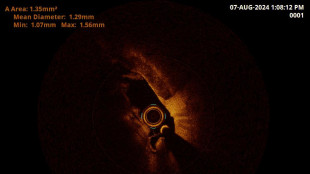

Melanoma, all'Int di Milano una 'biopsia virtuale' senza bisturi

Le lesioni studiate con microscopia confocale riflettente